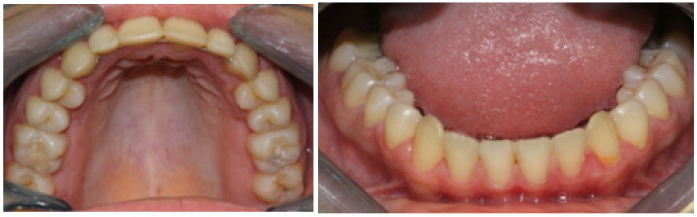

Figure 3B Post-treatment intra-oral occlusal view photographs.

Clinical results along with photographs and radiographs comparing pre and post treatment show dramatic esthetic and functional improvement, elimination of the bilateral posterior crossbite and correction of anterior guidance with a stable occlusion. Overjet and overbite was measured at between 1 to 2mm with a treatment time of a little over 12months (Figures 3&4). In addition, comparing pre with post treatment cephalograms shows radiographic evidence of an increased upper airway dimension.